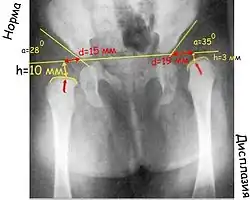

Большая часть головки бедра и вертлужной впадины у детей раннего возраста состоит из хрящей, которые невидимы на рентгеновском снимке, поэтому для чтения рентгенограмм применяют различные схемы.

Прежде всего проводят вертикальную срединную линию, она проходит через середину крестца. Проводят горизонтальную линию через У-образные хрящи, через нижние точки подвздошной кости (линия Хильгенрейнера). Через наружно верхний край, перпендикулярно горизонтальной линии проводят линию Перкина. Часто бывает, что на стороне поражения невозможно определить верхний край вертлужной впадины. В этих случаях пользуются методом Рейнберга: симметрично, на таком же расстоянии от срединной линии проводят вертикальную линию (перпендикулярно горизонтальной). Она и будет обозначать невидимый на рентгенограмме верхнелатеральный край впадины. Через края вертлужной впадины проводят касательную линию до пересечения с горизонтальной линией Хильгенрейнера. Образованный угол называется «ацетабулярный угол», или угол наклона крыши вертлужной впадины.

К вспомогательным линиям относят линию Шентона и Кальве. Линия Шентона (запирательно-бедренная дуга) в норме «представляет собой мысленное продолжение краниального края запирательного отверстия на медиальный краевой контур шейки бедра» (В. О. Маркс, 1978). При патологии (смещении бедра латерально и вверх) эта линия разрывается.

При дисплазии ядра окостенения появляются позже, размеры их меньше, они развиваются медленнее. В норме ядро окостенения головки бедренной кости большей своей частью располагается медиальнее линии Перкина и ниже линии Хильгенрейнера. При подвывихе и вывихе она смещается вверх и латерально. Ядра окостенения головки бедра появляются у девочек в 4-месячном, у мальчиков в 6-месячном возрасте.

Величина ацетабулярного угла в норме составляет менее 30° у новорождённых и около 20° у детей от 3 месяцев и старше.

«У нормального новорождённого угол наклона крыши (ацетабулярный угол) равен в среднем 25–29°. Угол наклона у грудного ребёнка в связи с прогрессирующим окостенением таза от месяца к месяцу уменьшается. К одному году жизни угол равен в нормальных условиях у мальчиков 18,4, у девочек – 20,0°. К 5 годам жизни он бывает меньше 15,0° у детей обоего пола. Углы наклона крыши, превышающие средние цифры, означают задержку нормального окостенения, то есть ту или иную степень дисплазии сустава. Незначительные отклонения от нормы исчезают обычно в первые месяцы жизни младенца» (В. О. Маркс)

Очень важный показатель, характеризующий дисплазию тазобедренного сустава, — величина h, характеризующая вертикальное смещение головки бедра. Это расстояние от линии Хильгенрейнера до центра головки бедра, то есть примерно до середины видимой на рентгенограмме метаэпифизарной пластинки бедренной кости (на 1–1,5 мм выше).

В норме величина h составляет от 9 до 12 мм. Уменьшение этого размера или различие его справа и слева указывают на дисплазию.

И ещё один важный показатель – величина d – показатель латерального смещения головки бедра относительно вертлужной впадины. Это расстояние от дна вертлужной впадины до линии h. В норме он не превышает 15 мм.